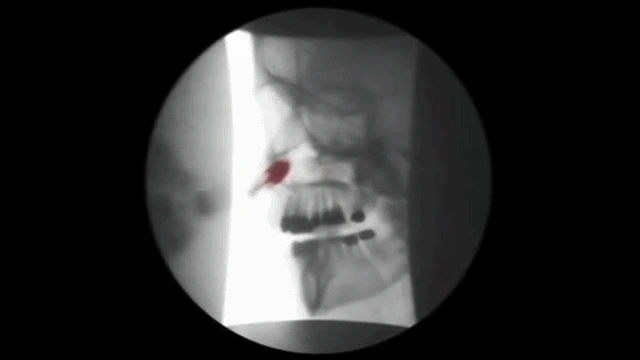

치료용 풍선을 코로 넣어 비강과

인두 사이에 위치한 두개 안면 구조물을

확장시켜 고유의 위치로 복구시키는 치료법

그림에서 처럼 풍선을 이용하여 틀어진 비중격을

바로잡고 비중격 교정기를 이용하여 비중격을

바른 위치로 교정하게 됩니다.

이치료는 만성비염환자의 심한 코막힘증에도

탁월한 효과를 나타냅니다.